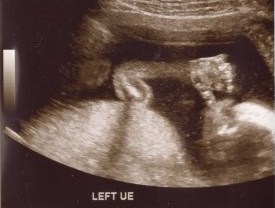

For an hour and a half today we watched, smiled, and cried at the images of our sweet baby boy. I learned a new kind of love today and my heart is full. I can't get enough of his little profile. We are so very blessed. Meet our little guy: